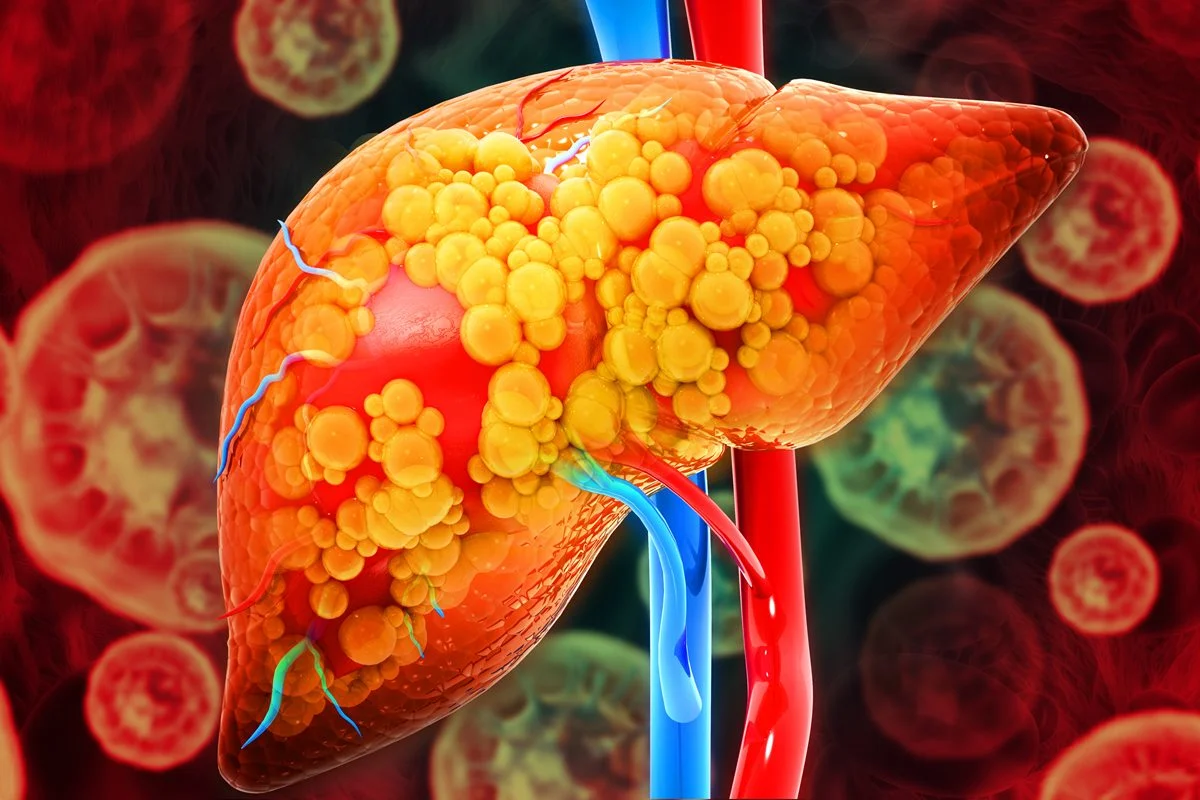

A condição de gordura no fígado acomete 30% da população mundial

Magicmine/Getty Images 3 de 4